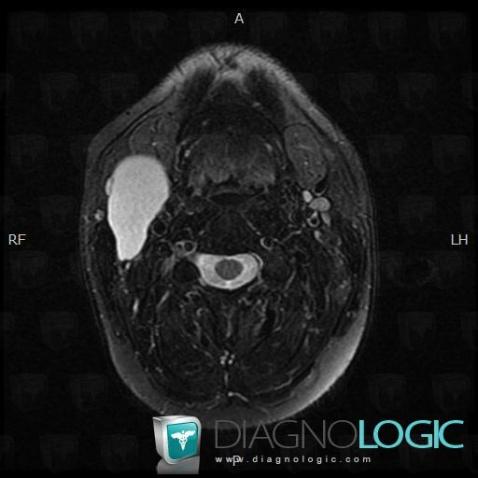

Second branchial cleft cyst, Deep neck spaces, MRI

Here is the specific information in the key image above:

- Diagnosis Second branchial cleft cyst (link to Branchial cleft cyst), Location(s) Deep neck spaces, with gamuts Cystic cervical mass